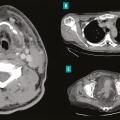

Les infections cutanées graves sont principalement représentées par les infections nécrosantes des tissus mous ou dermohypodermites bactériennes nécrosantes-fasciites nécrosantes (DHBN-FN). Bien que rares, elles sont associées à une mortalité élevée et à de lourdes séquelles à long terme. La principale difficulté réside dans l…

Cinq diagnostics différentiels des dermohypodermites bactériennes nécrosantes-fasciites nécrosantes (DHBN-FN) sont importants à connaître : la dermohypodermite bactérienne non nécrosante (DHBNN), le pyoderma gangrenosum, les atteintes ischémiques ou mécaniques, et l’infection sur pied diabétique. L’anamnèse, la recherche des anté…